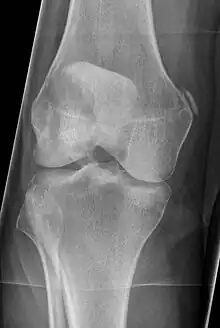

| Pellegrini-Stieda syndrome. Also visible is a fracture of the patella. |

Pellegrini–Stieda syndrome (also called Stieda disease and Köhler–Pellegrini–Stieda disease) refers to the ossification of the superior part of the medial collateral ligament of the knee. It is a common incidental finding on knee radiographs. It is named for the Italian surgeon A. Pellegrini (b. 1877) and the German surgeon A. Stieda (1869–1945).[1] While the eponym is credited to Pellegrini and Stieda, the condition was first discovered by Köhler in 1903, before any namesakes. Pellegrini-Stieda combines the aforementioned radiographic findings and concomitant medial knee joint pain or restricted range of motion.[2]

Diagnosis is typically made on radiographs demonstrating the Pellegrini-Stieda syndrome sign accompanied by pain or restriction of range-of-motion of the knee joint.[2] Pellegrini-Stieda syndrome sign is typically described by a longitudinally linear opacity, which is a process that is describes characteristic of calcification in the soft tissue located medial to the medial femoral condyle.[2] This calcification seen on imaging represents the ossification of the medial collateral ligament, which typically does not develop until approximately three weeks after the initial injury.[2]It is important to note to distinguish this radiographic finding from that of a medial femoral condyle avulsion fracture, which is an injury in which a pulling force of a tendon or ligament fractures away a piece of the bone from its attachment site.[2]